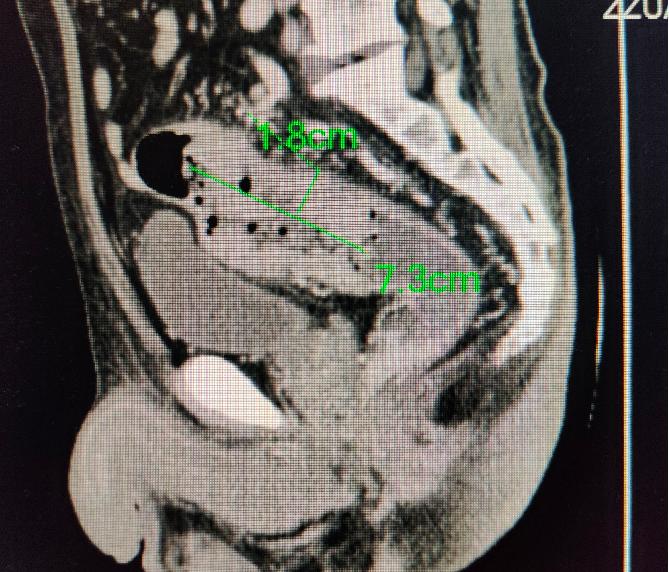

大致的测量了范围,厚约2cm,长度约7cm

我找到患者家属并当面进行了解释说明。由于情况比较突然,患者子女情绪激动,一时难以接受。稳定后,家属询问能不能马上手术切除。答案是否定的。因为肝上已经有了范围比较大的转移。也就是我们常说的癌症晚期。

圆圈内稍暗的部分为转移